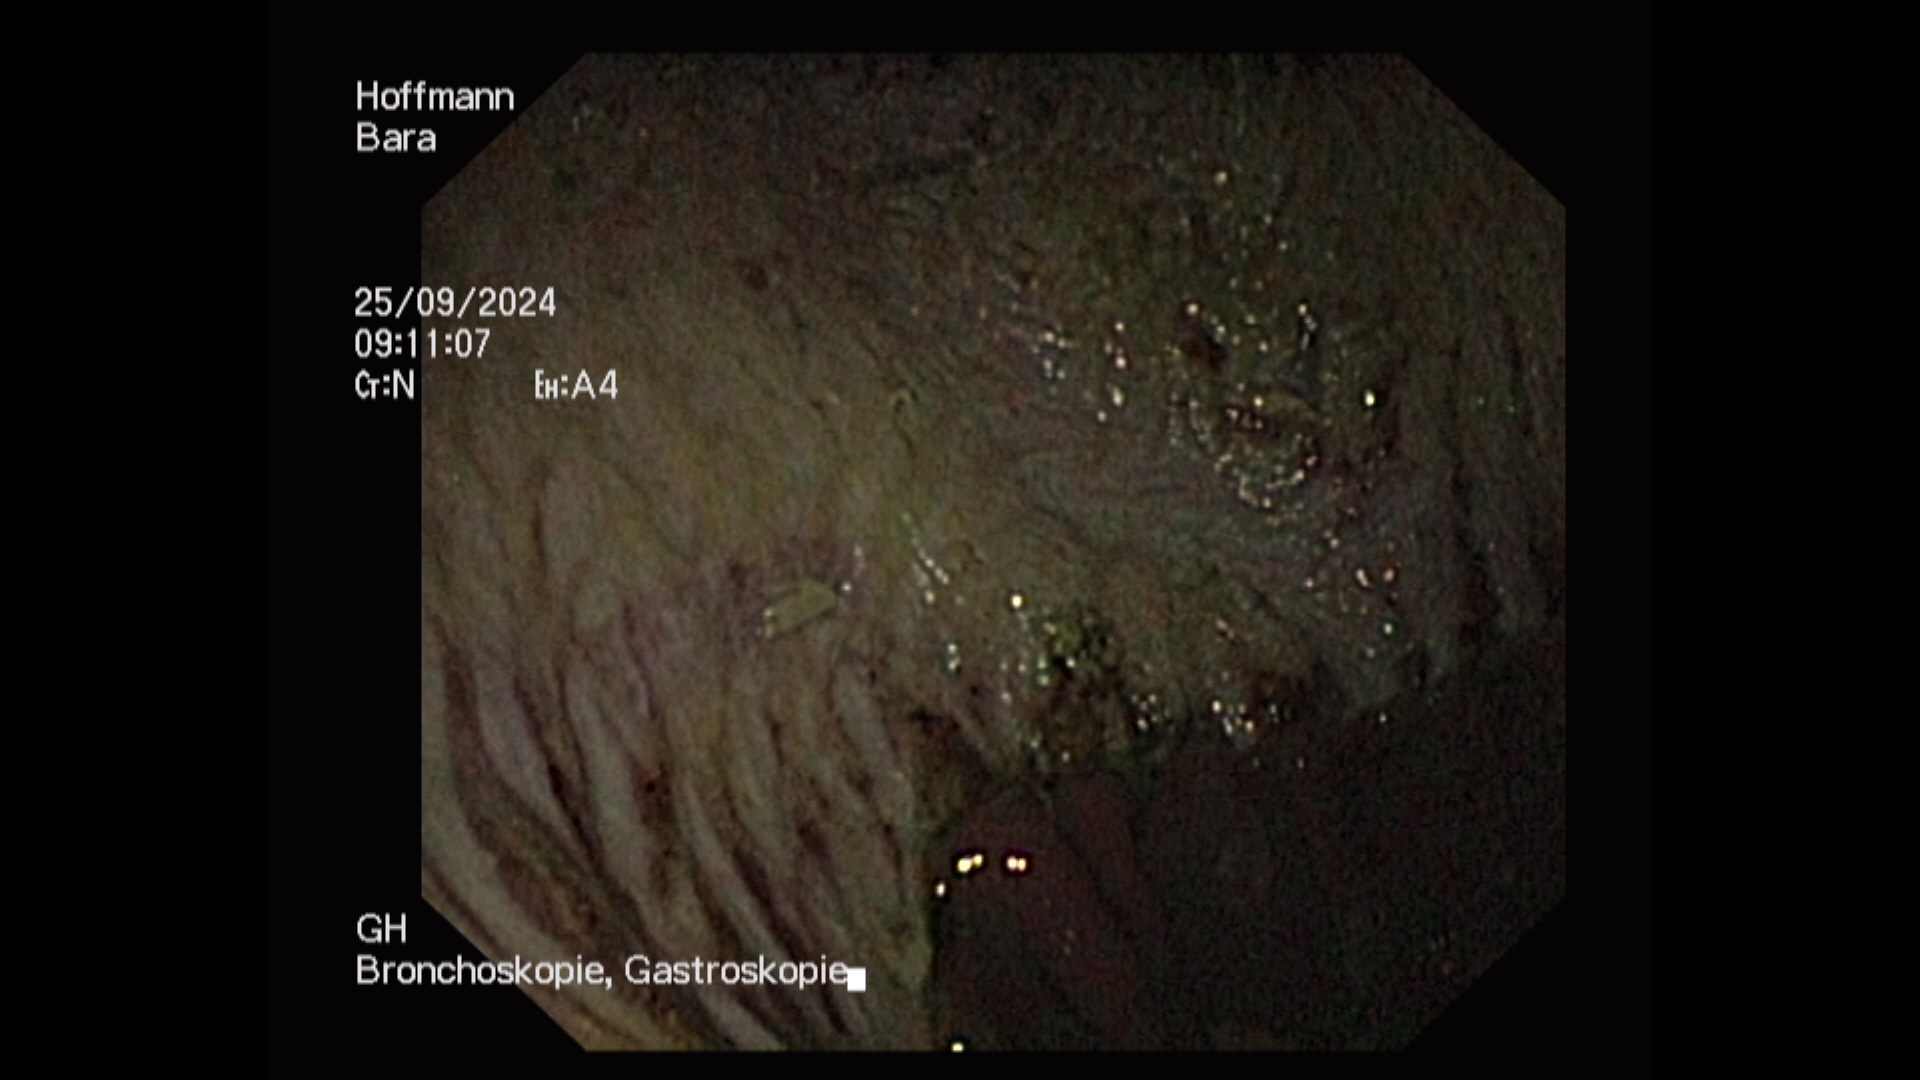

| • | Um den Stress bei der Gastroskopie zu minimieren und das Einbringen des Gastroskops zu erleichtern ist eine leichte Sedierung für die Untersuchung notwendig. Nach der Sedierung wird ein langer, flexibler Schlauch, der eine Optik trägt, durch die Nüster des Pferdes eingeführt und vorsichtig durch die Speiseröhre in den Magen vorgeschoben. Dabei werden Speiseröhre und Magen beurteilt. Nur bei einem nahezu vollständig leeren Magen ist eine genaue Untersuchung der Magenwände, der Schleimhaut und des Magenein- und ausgangs möglich. |

Besondere Aufmerksamkeit gilt auffälligen Bereichen, wie Rötungen, Blutungen oder Geschwüren. Es können darüber hinaus auch andere Probleme wie Magenentleerungsstörungen oder Parasitenbefall (z. B. Magendasseln) diagnostiziert werden. Falls notwendig, können während der Gastroskopie Proben entnommen und Fotos und Videos zur weiteren Auswertung angefertigt werden.